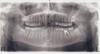

Сафари Опубликовано 8 октября, 2011 Поделиться Опубликовано 8 октября, 2011 Добрый день!Пожалуйста, посмотрите на панорамный снимок. Прицельных, к сожалению, не имею в наличии. Извините, если четкость панорамного снимка не позволяет диагностировать проблемы. Волнует несколько вопросов:1) Расположение зубов мудрости. Ни один из них еще не прорезался. Но снимок меня сильно настораживает. Наслушался рассказов о том, как болезненно их удаляют, и какие осложнения бывают. Сейчас они меня не беспокоят, но я предчувствую наихудший сценарий, что они начнут разрушать корни "семерок", и придется что-то с ними делать. Существуют ли способы сохранить зубы, изменив направление их роста? 2) Нижняя левая "шестерка". Была депульпирована 15 лет назад в детском возрасте. С тех пор, как мне кажется, поменяли пломбу лет 13 назад на "более хорошую" (по словам врача обычной гос.поликлиники). Все равно материал дал усадку, и сейчас от нее мало что осталось. Обращался к ортопеду по случаю крошения стенки этого зуба. Делали прицельный снимок. Врач сказал, что каналы не запломбированы, зуб надо перелечивать, пломбировать все каналы полностью, и только после этого делать коронку.Действительно ли требуется перелечивать каналы? Какие могут быть осложнения? Что сейчас в каналах, если они не запломбированы? Там пустота или живые ткани, или "бомба" которая может рвануть в любой момент? Я могу ошибаться, но мне кажется что бывали моменты когда этот зуб ныл, реагировал на горячее. Было это давно - около 10 и 5 лет назад. Такое могло быть? У меня остался живой нерв? Что ожидать от перелечивания? 3) Нижняя правая "шестерка". Лечили глубокий кариес одновременно с предыдущим зубом (15 лет назад). Пломбу с тех пор один раз поменяли, тоже очень давно. Врач сказал, что ее надо менять снова. Можно ли сказать по снимку насколько велик шанс поменять эту пломбу на новую, не удаляя нерв? Много ли зубной ткани разделяет пломбу и пульпу, чтобы была возможность препарировать полость для новой пломбы? Я вообще правильно понимаю, что лечение кариеса имеет смысл, только пока полость не дошла до пульпы? Или спасти нерв можно даже при оголении пульпы в процессе сверления зуба? 4) Аналогичный вопрос по нижней левой "четверке". Стоит пломба, которую вроде бы пора заменить. 5) Наконец, самый беспокойный вопрос. В июле мне лечили глубокий кариес в нижней левой "семерке". Зуб до вмешательства не болел и не беспокоил вообще. Поставили "световую" пломбу. После этого появилась боль при накусывании. По словам врача она должна была пройти через неделю-две. Боль не прошла, причем зуб болит не просто при накусывании, а только при определенном небольшом сдвиге нижней челюсти вправо. То есть при точечном воздействии верхнего зуба на определенный участок поверхности нижнего зуба. Если начать жевать твердую пищу, то легко можно попасть на больное место и получить пронзающую боль. А обычное "ровное" сжатие челюстей не вызывает никаких ощущений. Недавно зуб стал беспокоить еще и реакцией на горячее - начинает "ныть" не очень сильно.Что с зубом? Плохо поставили пломбу? Или надо было нерв удалять? 6) Бросается ли в глаза что-то еще, о чем следует побеспокоиться?Спасибо за ответы. Ссылка на комментарий